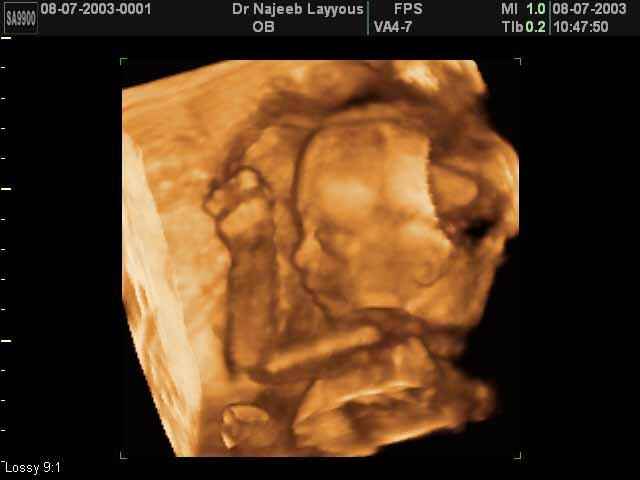

- صور جانبية لرأس الجنين

صور جانبية لرأس الجنين بجهاز الالتراساوند ثلاثي الأبعاد | الدكتور نجيب ليوس